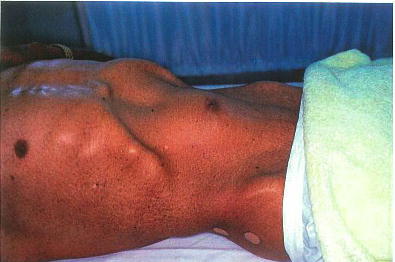

67歳の男性。腹部のしこりを主訴に来院した。2年前から腹部のしこりに気付いていたが,最近急に大きくなってきた。触診上腫瘤は拍動性である。腹部の写真を別に示す。

この患者の診断に有用なのはどれか。

正解 c

診断 腹部大動脈瘤